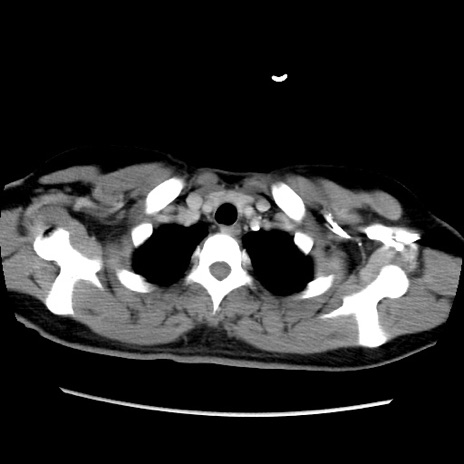

症例39(横断像)

【症例】40歳代女性

【主訴】上下腹部痛

【現病歴】2日目から下腹部痛あり。夜間は痛みで眠れなかった。昨日より上腹部痛と下痢が出現。臥位で痛みは軽快したため、休んでいた。本日になって臥位でも立位でも痛みが強くなってきたため救急要請。

【既往歴】子宮内膜症

【身体所見】部:平坦・軟、左上下腹部に圧痛あり、反跳痛あり。

【データ】WBC 21800、CRP 26.78